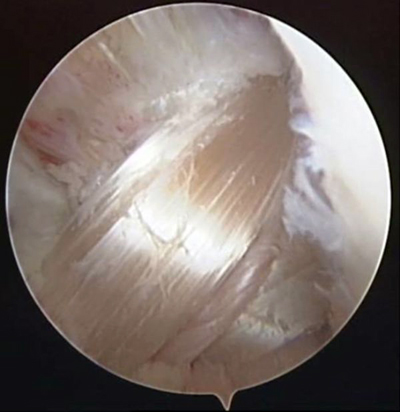

關(guān)節(jié)鏡下見重建的前交叉韌帶